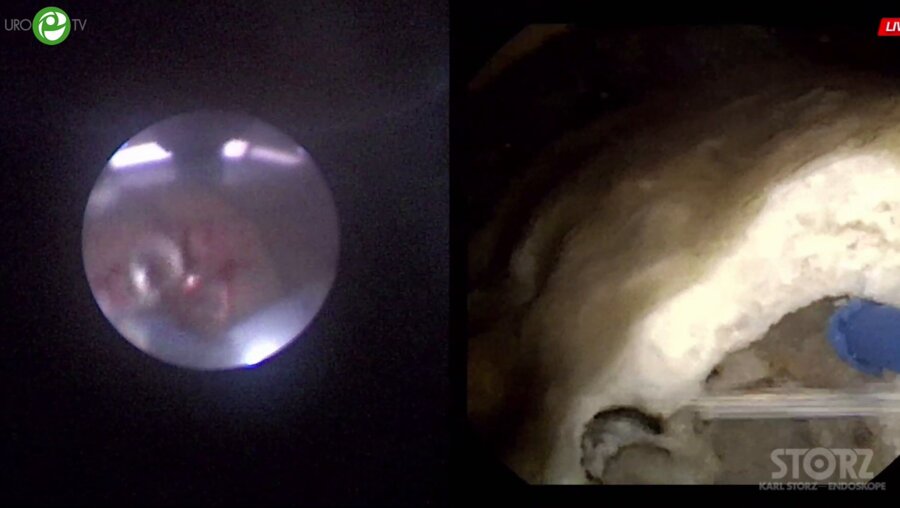

Видео